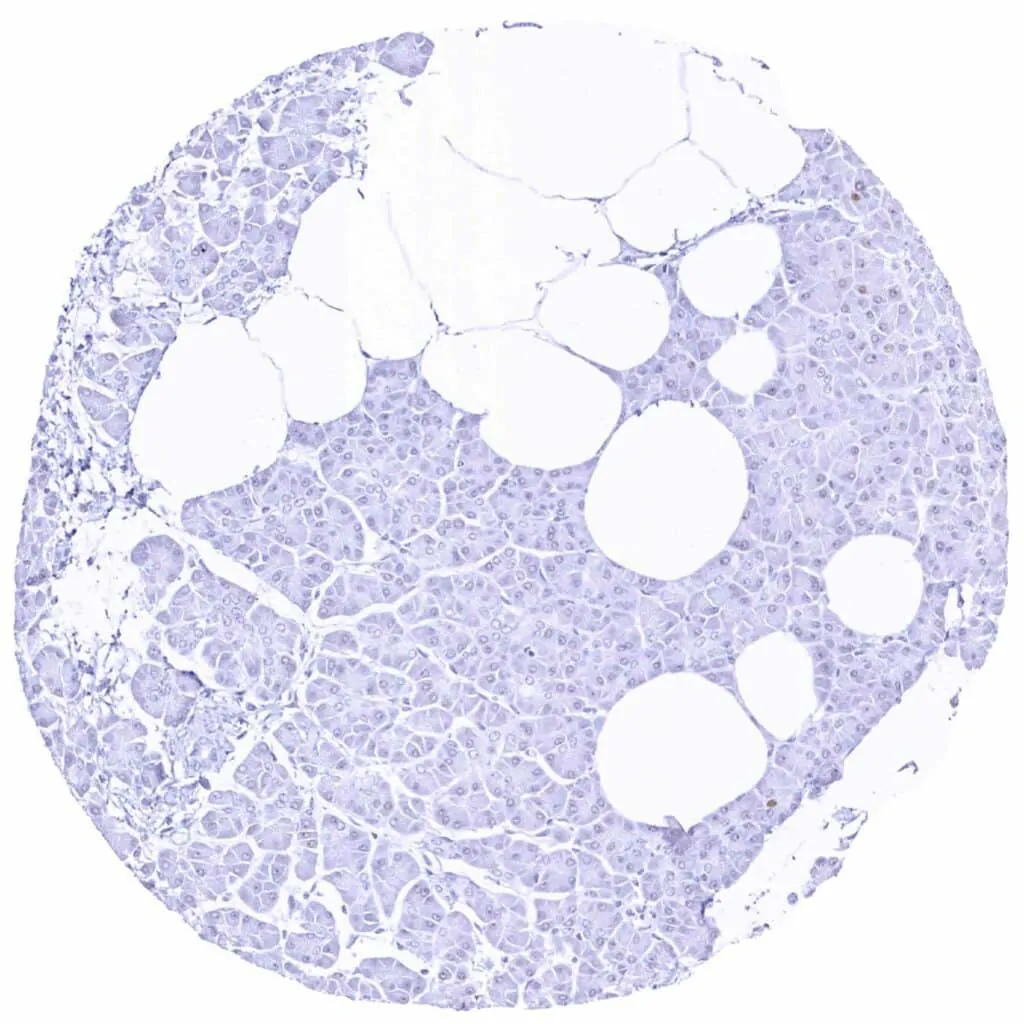

Liver